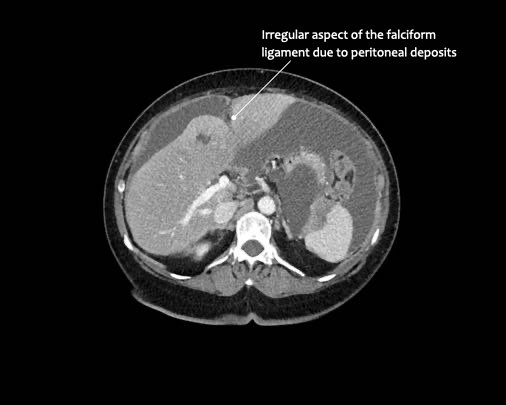

- Dây chằng liềm

Ở vùng bụng trên, cơ hoành và dây chằng liềm cần được chú ý đặc biệt.

Các vị trí điển hình khác bao gồm rãnh cạnh đại tràng, túi cùng trực tràng-bàng quang hoặc trực tràng-tử cung, dây chằng liềm và mặt bụng của cơ hoành.